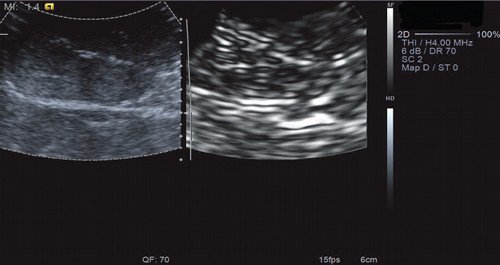

Рис. 14. Эластография с методикой ARFI. Объемное образование печени мягкой консистенции с жесткими включениями (вариант эластограммы № 3).

Рис. 15. Эластометрия объемного образования печени. Показатель СРПВ (скорость распространения поперечной волны) в центральных отделах опухоли был от 3,38 до 3,96 м/с - фиброзные изменения в центральных отделах ФНГ.

Рис. 16. Эластометрия объемного образования печени. Показатель СРПВ (скорость распространения поперечной волны) в периферических отделах опухоли был от 2,41 до 2,90 м/с.